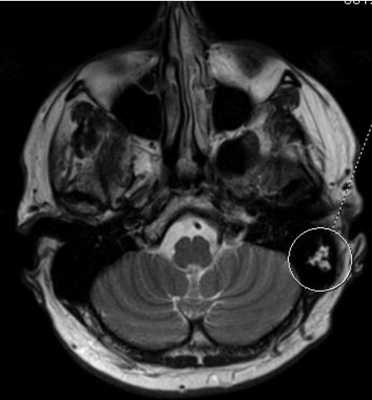

МРТ головного мозга. Аксиальная Т2-взвешенная МРТ. Фрагмент ММУ. Холестеатома слева.

Вестибулокохлеарный нерв (VIII) состоит из 4 пучков. Опухоли происходят обычно из вестибулярной его части. Шваннома - инкапсулированная доброкачественная (градация 1) опухоль, происходящая из дифференцированных неопластических шванновских клеток оболочек периферических нервов. Невриномы ММУ составляют около 3% опухолей головного мозга. Часть шванном (двухсторонние слуховых нервов) связана с НФ 2 типа. Пик частоты между 40 и 60 годами. Растут медленно и крайне редко малигнизируются. Клинические проявления связаны с нарушением функции нерва и компрессией ствола. Шваннома может происходить из любого отрезка по ходу нерва и хорошо прослеживается при МРТ области ММУ. Невринома видна как на Т2-взвешенных, так и на Т1-взвешенных МРТ в виде округлого образования. Невриномы хорошо и равномерно усиливаются после МРТ с введением контрастного вещества. Невриномы области цистерны могут иметь компонент во внутреннем слуховом проходе, особенно, хорошо видимый при МРТ головного мозга с контрастированием. Изредка встречаются невриномы полностью расположенные внутри канальца. Они составляют наибольшую диагностическую сложность при МРТ, требуют тонких срезов и контрастирования. Менингиомы ММУ обычно типично расположены и при МРТ имеют характерную форму и типичные черты при МРТ с контрастированием. Однако редко встречаются внутриканальцевые менингиомы. При МРТ они неотличимы от неврином. Холестеатомы при МРТ имеют смешанную интенсивность сигнала, в зависимости от их содержимого. На диффузионно-взвешенных МРТ холестеатомы обычно яркие.

При МРТ головного мозга картина неспецифическая и зависит от содержимого кисты. Если она не содержит жира, топри МРТ головного мозга эпидермоидная киста имеет ликворную интенсивность сигнала. В таком случае эпидермоидная киста трудно отличима от арахноидальной, хотя, как правило, не столь однородная. На FLAIR томограммах и диффузионно-взвешенных МРТ головного мозга содержимое эпидермоидов светлее ликворного. Жировое содержимое, такие эпидермоиды еще называют холестеатомой, приводит к высокому сигналу на Т1-зависимых МРТ головного мозга. Видимо, он обусловлен липидами, но не холестеролом. На Т2-взвешенных МРТ головного мозга он менее интенсивен чем ликвор. Контуры эпидермоидов на МРТ всегда четкие. Холестеатомы составляют всего 3-5% от эпидермоидов. В 15-20% случаев встречается кальцификация по переферии кисты. Редко наблюдается усиление стенок кисты при МРТ головного мозга с контрастированием.